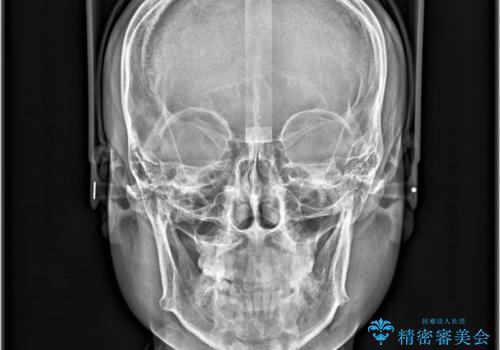

非抜歯矯正で八重歯を改善|短期間8か月で美しい歯並びに|インビザラインライト上顎のみで矯正

- 「八重歯を治したい」との主訴でご来院された患者様です。。

非抜歯で上顎のみインビザラインライトを使用して矯正を行いました。